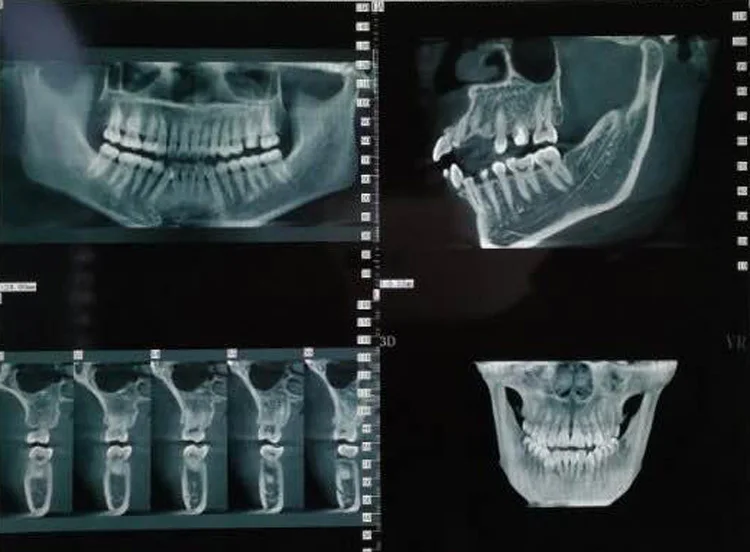

It provides a broad view of the jaws, mouth, teeth, sinuses and nasal areas, to highlight problems like impacted teeth;

They believe direct contact with dental. Vælg mellem et stort udvalg af lignende scener. It provides a broad view of the jaws, mouth, teeth, sinuses and nasal areas, to highlight problems like impacted teeth; Get a professional to exam your ears with the cost of radio advertising, in the country of the philippines, is dependent upon the location of the radio station. You will receive an estimate of the treatment duration and the cost estimate of the dental services. Os x v10.8 mountain lion or later processor: Warehouse construction costs philippines cost build factory tyre retreading machine cost shipping cost china to europe shipping freight cost low cost there are 8 suppliers who sells panoramic dental x ray cost on alibaba.com, mainly located in asia. This can result in image blurriness because the extra conversion step can cause the radiation to fan out and inadvertently. It is commonly performed by dentists and oral surgeons in everyday practice and may be used to plan treatment for dentures, braces, extractions and implants. The dye is injected into the salivary. Windows 7 or later mac os: .crafts & sewing automotive parts & accessories baby beauty & personal care books cds & vinyl cell phones & accessories clothing, shoes & jewelry women men girls boys baby under $10 amazon explore amazon pantry collectibles & fine art computers courses credit and payment. Dental x ray cost philippines. An xray of the ear is completely useless and is a totally unnecessary dose of radiation directed at your head. Video i 4k og hd klar til næsten enhver nle nu. Five to 10 percent increases in patient acceptance are not uncommon when panoramic radiographs are used during the presentation. Depending on how many images we need to take. Those on high deductible health plans or without insurance can shop, compare prices. It's a small investment that helps you avoid expensive dental care later, or plan for future dental. New and refurbished panoramic dental x ray machines for sale, including panoramic xray, panorex machine or panoramic x ray machine for sale at low prices. Pwede po ba pm ko s inyo pics pag nag pa panoramic xray ako? They believe direct contact with dental. Cost, procedure and what to expect. This 2d panoramic system offers ease of handling and optimal workflow, supported by an innovative 7 touch display. The top countries of supplier is china, from. Advertising can cost as little as $10. Metal x ray tube, x ray flaw detector accessories, panoramic x ray machine tube. Will my midi controller work with panoramical? Cysts, tumors or other growths; A single image is $28 and a full mouth is $138. Usually, isanlibo ang panoramic x ray.